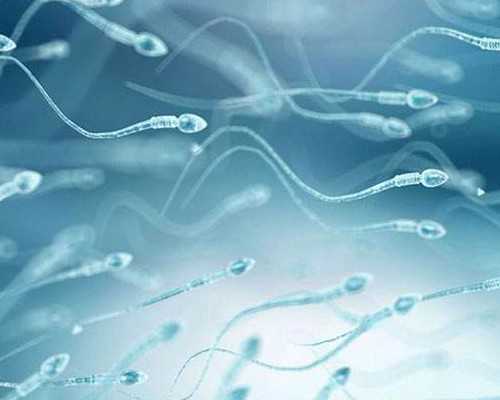

福州試管嬰兒洗精技術(shù)有哪些好處?聊聊常用的精子洗滌方法

高齡夫妻備孕成功一半靠男性:提升精子質(zhì)量的關(guān)鍵時(shí)期與營(yíng)養(yǎng)補(bǔ)充方案